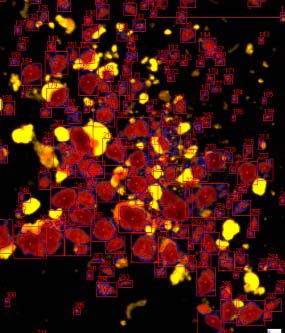

ICC4-230是胰島細(xì)胞自動(dòng)化計(jì)數(shù)儀器:

2. 全新的暗場(chǎng)照明提高了小顆粒檢測(cè)、圖像分割的能力,并且可以計(jì)數(shù)純化的未染色樣本;

細(xì)胞自動(dòng)檢測(cè),SNR掃過RGB范圍后的閾值

先進(jìn)的自適應(yīng)分區(qū)算法